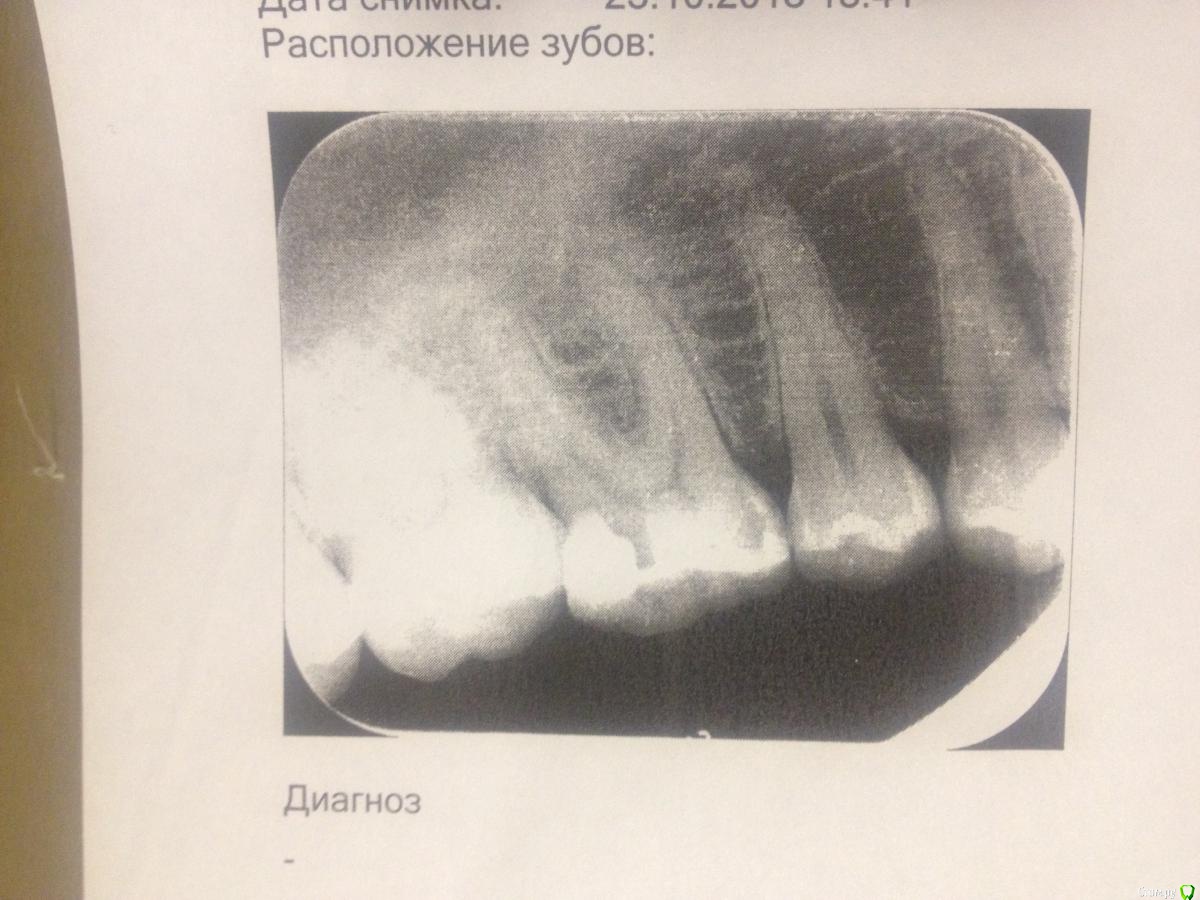

Darya90 Опубликовано 23 октября, 2018 Поделиться Опубликовано 23 октября, 2018 Добрый день!Неделю назад заболел зуб (после того, как наелась мороженым...). 1й день была периодическая резкая ноющая боль, на 2й день также приступы, но гораздо слабее, на 3й день вроде не было боли, но затем характер боли изменился, точнее была даже не боль, а ощущение того , что зуб мешается и к тому же он начал шататься.Врач на основании осмотра и снимка поставила диагноз периодонтит и назначила лечение стоимостью 12-14 тыс, хотя клиника вроде как позиционируется как клиника с ценами средними/ниже средних. Произошел периодонтит вследствие некачественной предыдущей пломбы - год назад у меня отвалился кусок зуба и его заделывали пломбой.Оцените, пожалуйста, снимок зуба. Так ли там все запущено и соответствует ли цена действительности? Зуб вроде как 3хканальный. P.S. возможно снимок надо перевернуть? Больной зуб - нижняя шестерка. Ссылка на комментарий

сирена Опубликовано 23 октября, 2018 Поделиться Опубликовано 23 октября, 2018 Да,там периодонтит.Нормальная цена,как по мне.У нас в Ростове примерно такие же. Ссылка на комментарий